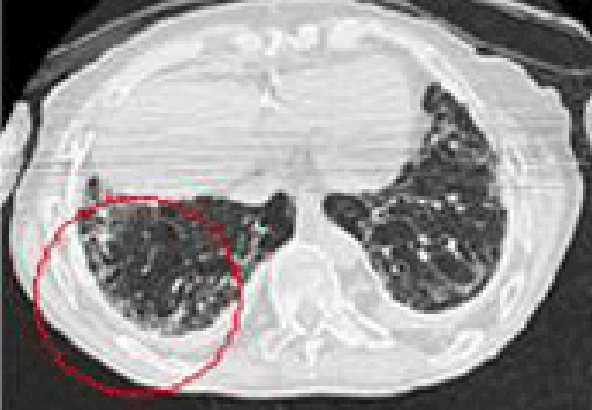

원발성[原發性] 악성중피종(잠복기 약 20~35년)

잠복기가 약 20~35년에 걸친 석면으로 인한 원발성 악성중피종에 대한 CT사진

석면 노출이 발생원인으로 알려진 대표적인 암으로 중피세포가 둘러싸고 있는 흉막, 복막, 심장막 등에 발생

• 흉막중피종 : 흉막이 중피종으로 두꺼워져 폐의 부피가 감소

• 질병분류코드 : C45(중피종), C450(흉막의 중피종), C451(복막의 중피종), C452(심장막의 중피종), C457(기타 부위의 중피종) (www.koicd.kr, 질병분류정보센터 참조)